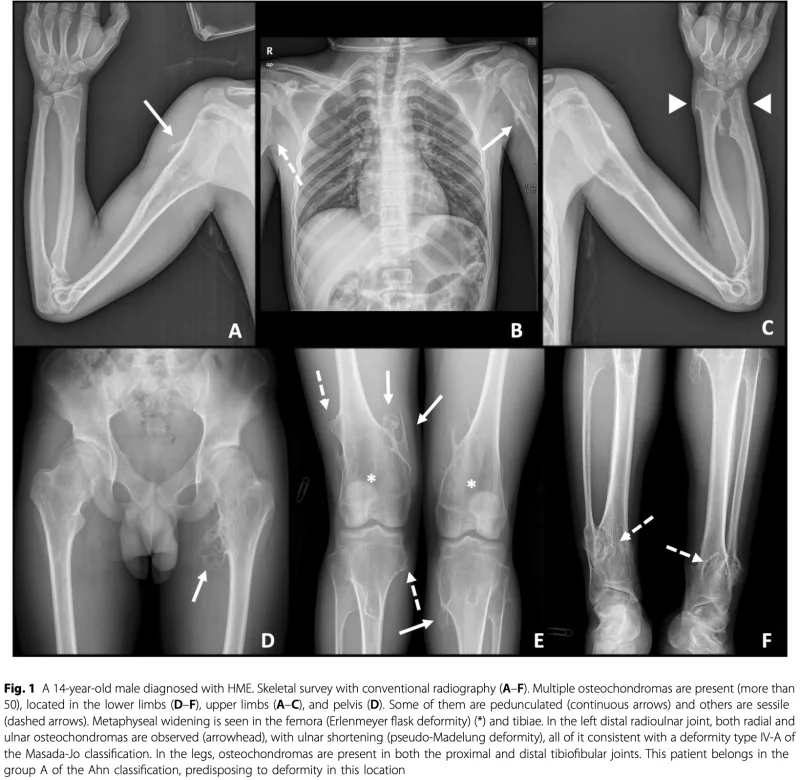

骨の関節に近い部分(骨幹端)に骨の表面から隆起した腫瘍(骨軟骨腫)が多数認められます.

腫瘍によって, 肥大, 短縮, 弯曲などの変形も合併しています.

大学病院から, 遺伝性多発性外骨腫の中学生が紹介されて受診.

野球のプレー中に腕の痛みが出るため, 上腕骨の腫瘍切除を希望されていました.

診察すると, 上腕骨内後方に硬い隆起を触れ, 肘の曲げ伸ばしで摩擦感あり.

冬休み中の手術を希望とのことで, 術前検査をオーダーしました.